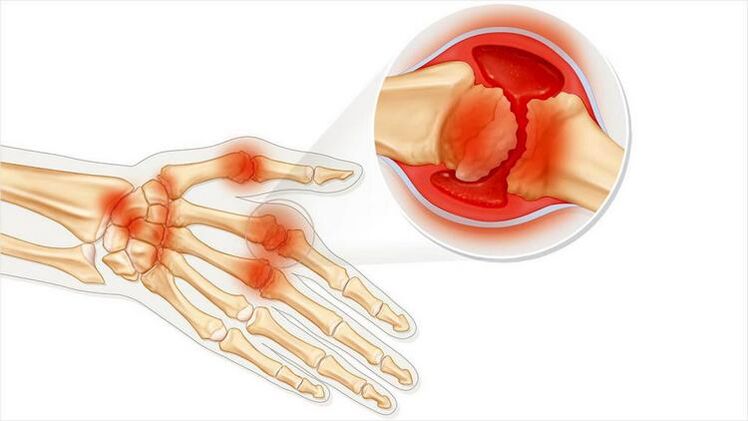

Arthritis is a condition of joint inflammation.The main symptoms are swelling and redness.The lining of the joint is destroyed, causing pain that is often unbearable.

The names of these two diseases have a common root: "arthritis."If you translate that from the Greek, you get "union."Both diseases are associated with joint problems and pain.Such conditions occur with severe negative feelings and discomfort.Lesions associated with the cartilage layer limit and complicate movement.

Arthritis has the following characteristics:

- If the skin near the joint becomes red, you may have a fever.

- Changes in the appearance of joints.

- tumor.

- Pain when moving.

- An unpleasant sensation when pressing on the joint.

- Arthritis may be an infectious disease.Then all the symptoms corresponding to an infection appear: nervous breakdown, fever, chills.

Arthritis can affect a single or multiple joints.It occurs with acute pain, or it occurs gradually and leads to chronic disease.A dull pain will then develop.